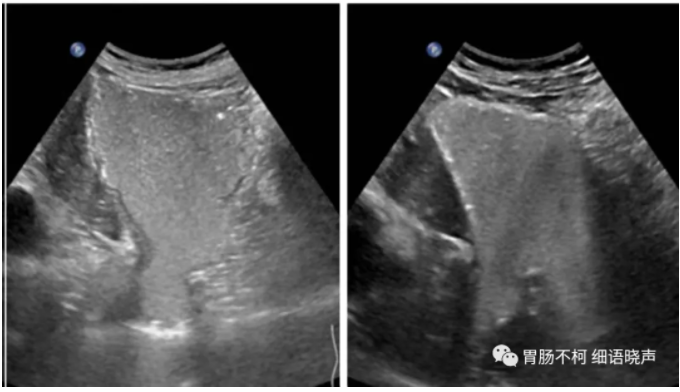

滑动型:EGJ上移,膈肌裂孔内径正常或增宽(正常解剖内经1.8-2.5cm),膈上疝囊及膈下胃呈“葫芦状”,“烧瓶状”,吸气、增加腹压、右侧卧位或二次充盈时疝囊及膈肌裂孔增大,造影剂在裂孔上下往返,膈上疝囊壁厚度及回声与胃壁一致相延续。

下图是不同表现的滑动型食管裂孔疝:宽窄不一的食管裂孔管径、大小不一的疝囊、或正常或变钝的HIS角,部分病例可见疝囊壁与胃壁回声及厚度一致的延续: